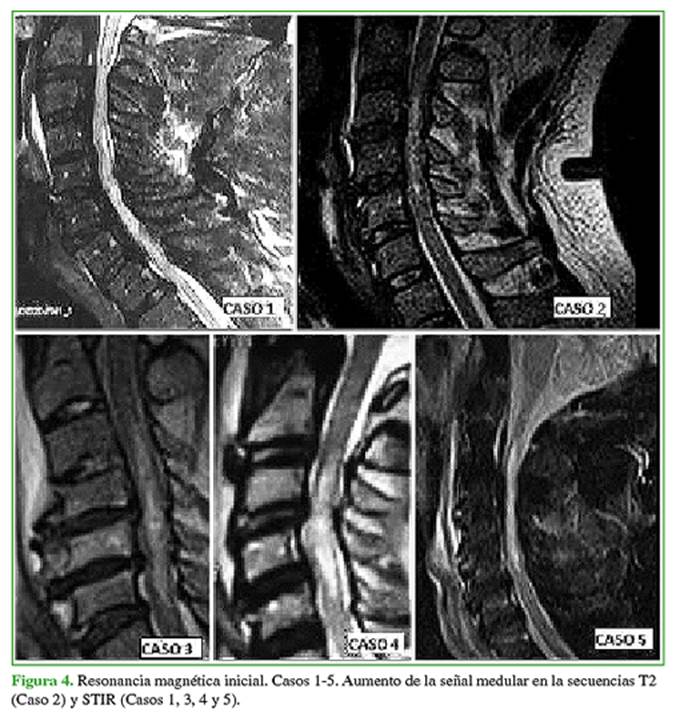

Todos los pacientes tenían imágenes de topografía medular hiperintensas en la secuencia de T2 de RM de gran extensión, con compromiso de múltiples niveles cervicales (Figura 4).

Se describieron las siguientes variables de estudio: edad, sexo, comorbilidades, antecedente traumático, tiempo preoperatorio (>72 h o <72 h), estado neurológico inicial según la escala de la American Spinal Injury Association (ASIA),23 tipo de OLLP según la clasificación morfológica: (A) continua, (B) segmentaria, (C) combinada y (D) limitada al espacio discal (Figura 1),24 extensión de la mielopatía según los niveles cervicales (imagen hiperintensa en la secuencia T2 de RM), tratamiento realizado (quirúrgico o conservador), tipo de cirugía (técnica y vía de abordaje), evolución neurológica posterapéutica (estable, mejoría o deterioro neurológico) y complicaciones (relacionadas con el trauma y la intervención).